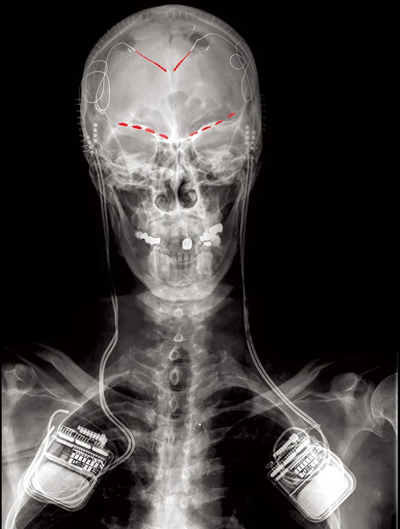

研究人员将记录电极(红线)和双向脑刺激和记录植入物植入四名患者体内,试图弄清导致他们慢性疼痛症状的原因。

每个患者都接受了手术,将神经记录和刺激平台植入他们的大脑。该设备是便携式的,允许每位患者进行他们的生活并记录代表他们日常中枢疼痛经历的数据。手机应用程序会定期提醒患者注意他们当前的疼痛程度,并记录来自神经植入物的 30 秒脑电波数据(皮层脑电图和局部场电位)。